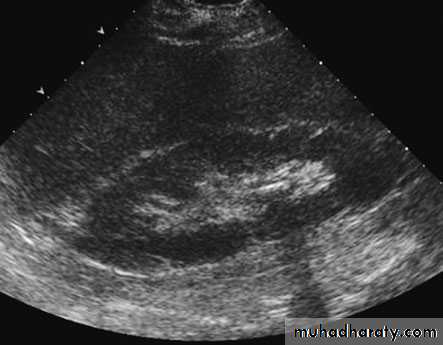

ULTRASONOGRAPHY (U/S )Structural study to differentiate cystic or solid masses, hydronephrosis, renal size, renal cortical thickness, and stones.

The volume of urine in the bladder before and after micturition (post void residue) can be calculated, and even tiny filling defects within it detected.

The prostate